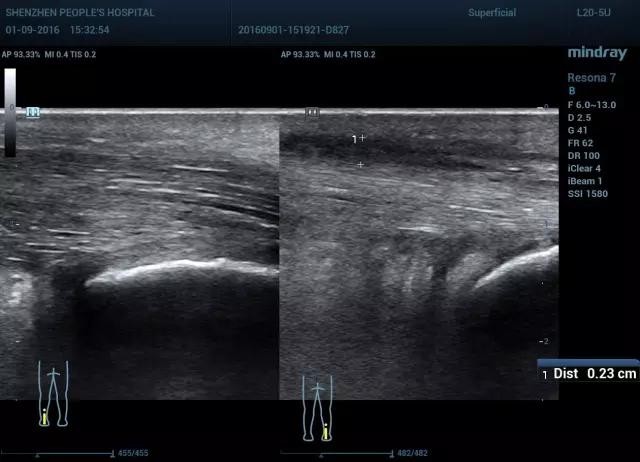

图9 腱周炎长轴双侧对比(图左 正常,图右 腱周增厚,回声减低,跟腱走行正常)

图10 腱周炎短轴双侧对比(图左 正常,图右 腱周增厚,回声减低,跟腱走行正常)